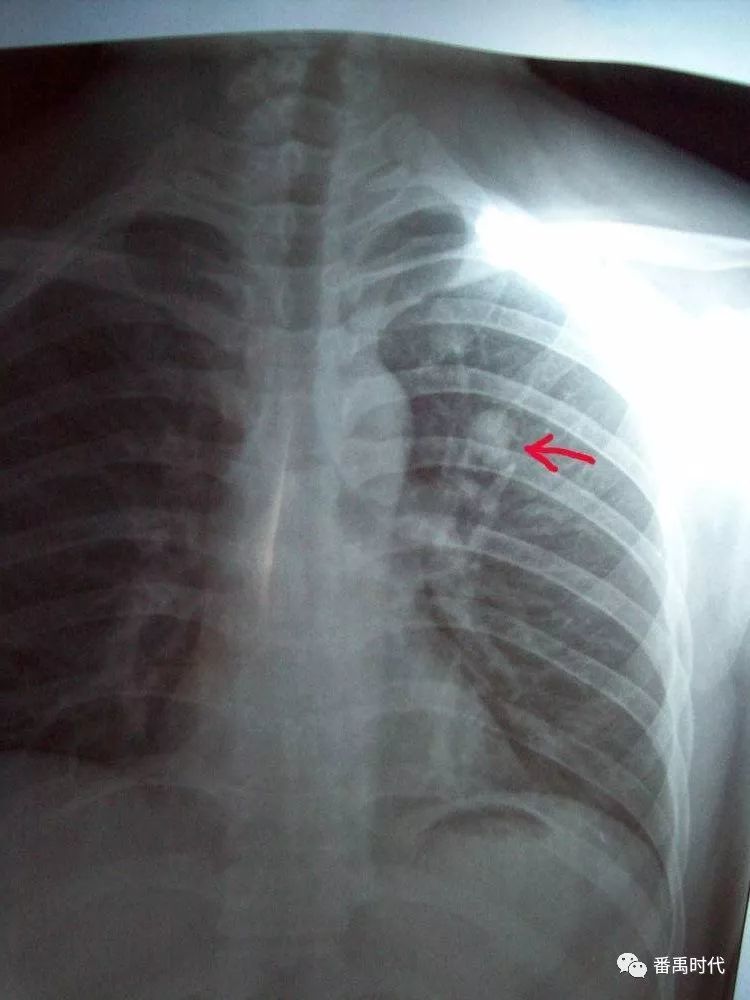

肺纹理增粗肺小结节胸片在告诉你什么

a示两肺弥 漫结节与片状密 度增高阴影.

肺部结节影大多不是肺癌

胸腔积液的x光胸片